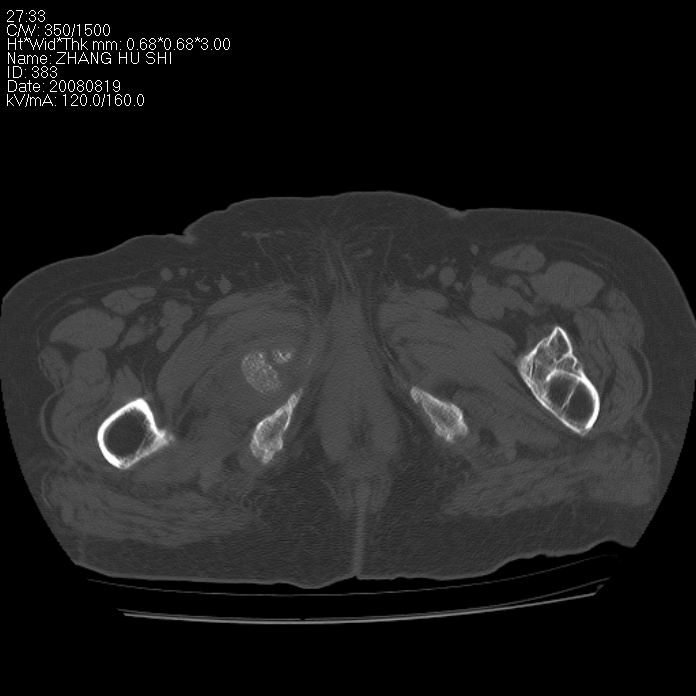

标题: CT15287:女 93岁 右髋关节疼痛 原左侧粗隆间骨折 CT发现右耻 [打印本页]

标题: CT15287:女 93岁 右髋关节疼痛 原左侧粗隆间骨折 CT发现右耻

支持转移

支持转移并周围软组织侵犯右闭孔内肌侵犯,但tb不能完全除外。

耻骨软骨肉瘤可能性大